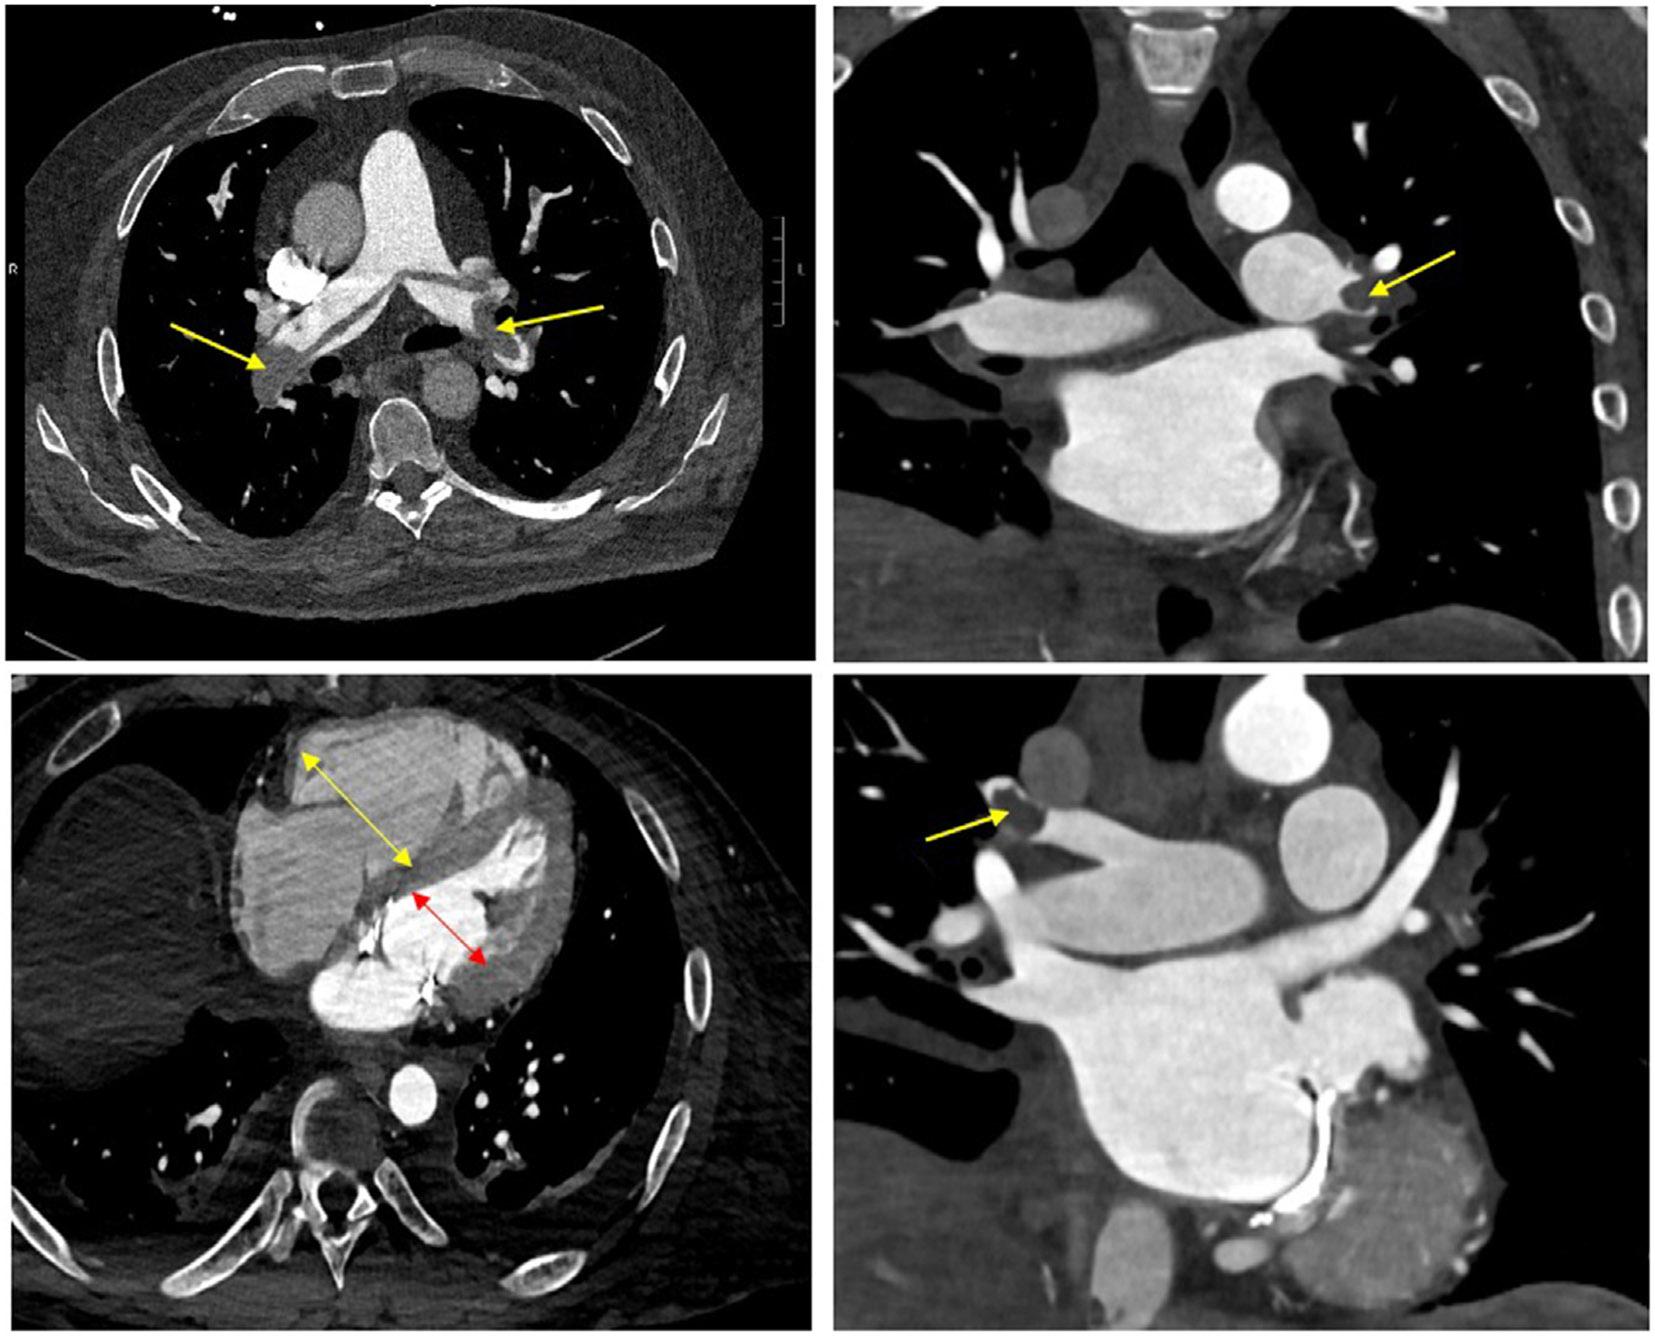

Pulmonary embolism (PE) is a common cardiovascular disease diagnosis in emergency departments that can be associated with significant morbidity and mortality. One of the first steps after diagnosing PE is to risk stratify for adverse outcomes using risk scores such as PE Severity Index and European Society of Cardiology risk scheme. While intermediate- and high-risk PE patients should be admitted to the hospital, there is increasing evidence to support early discharge and home-based anticoagulation therapy for low-risk patients. The Hestia criteria encompass many of the clinicians' considerations for who may be suitable for early discharge, considering both medical and social factors. Additionally, professional guidelines have provided algorithms on determining which low-risk patients may be suitable. Despite this, low-risk acute PE patients are still often admitted for inpatient treatment. In this review, we present a case-based approach on how to risk stratify and evaluate patients who may be good candidates for early discharge and home therapy.

肺栓塞(PE)是急诊科常见的心血管疾病诊断,可导致严重的发病率和死亡率。PE 诊断后的第一步是使用风险评分(如 PE 严重程度指数和欧洲心脏病学会风险方案)对不良结局进行风险分层。虽然中高危 PE 患者应住院治疗,但越来越多的证据支持对低危患者进行早期出院和家庭为基础的抗凝治疗。Hestia 标准考虑了许多医生认为适合早期出院的因素,包括医疗和社会因素。此外,专业指南还提供了确定哪些低危患者可能适合的算法。尽管如此,低危急性 PE 患者仍经常住院接受治疗。在这篇综述中,我们提出了一种基于病例的方法,用于对可能适合早期出院和家庭治疗的患者进行风险分层和评估。